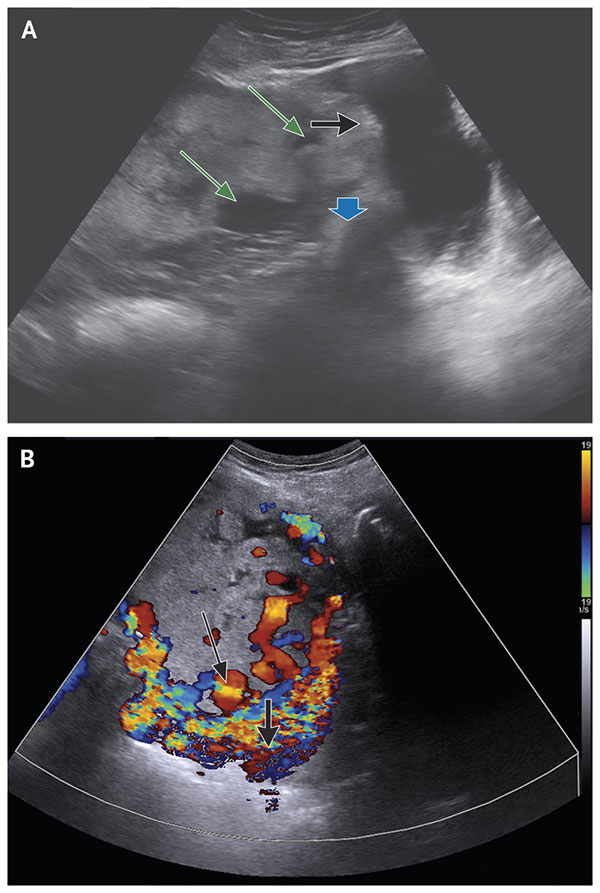

سنگ کیسه صفرا چطور تشکیل میشود و درمان آن چیست؟

سنگ کیسه صفرا زمانی تشکیل می شود که موادی مانند کلسترول یا بیلی روبین در صفرا (ماده ای که توسط کبد تولید و در کیسه صفر...